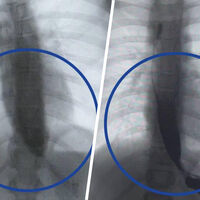

Врачи Детского клинического центра им. Л.М. Рошаля спасли девятилетнюю девочку с редким заболеванием — ахалазией кардии, из-за которого ее пищевод был расширен в пять раз. Об этом сообщили в пресс-службе минздрава Московской области.

Медики рассказали, что пищевод пациентки из-за патологии был расширен до четырех сантиметров, при норме в семь — десять миллиметров.

Операция прошла успешно, что уже на следующий день показало контрастное исследование — пища стала беспрепятственно поступать в желудок.